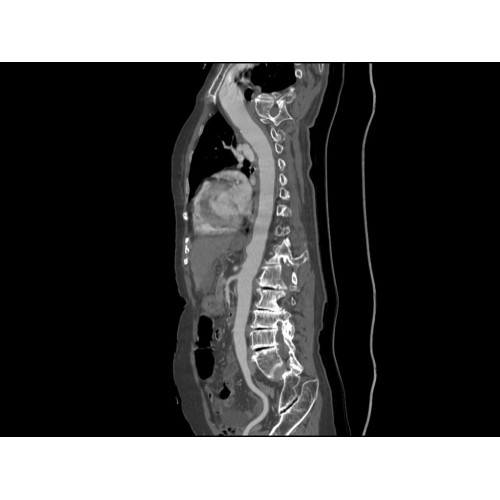

Позволяет проводить комплексные исследования всех анатомических зон, включая нейровизуализацию, ангиографию, исследования органов грудной и брюшной полости. Особенно эффективен для раннего выявления онкологических заболеваний.

Специализированные исследования